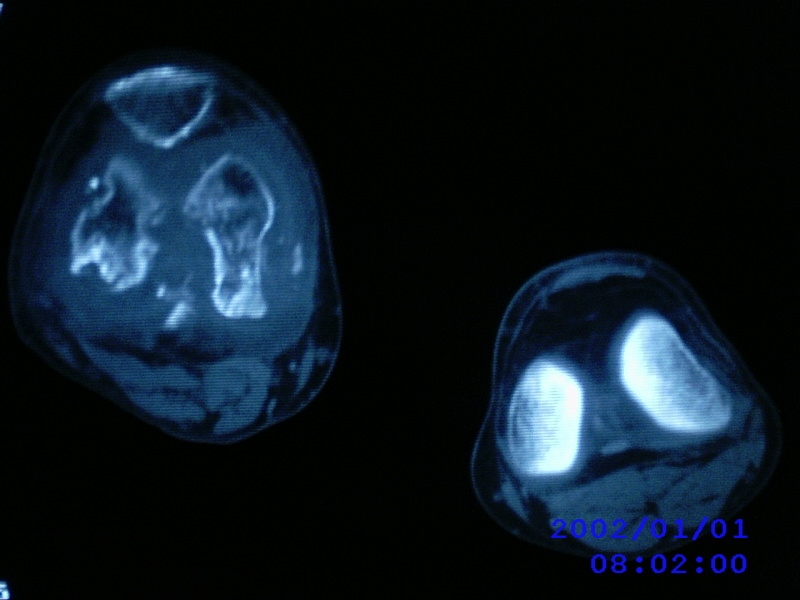

患者,男性,57岁,右侧膝关节疼痛伴肿脹10余年,加重一个月。

关节积液,关节间隙变窄,边缘骨破坏。考虑膝关节tb

关节积液,关节间隙变窄,骨质疏松,多发骨破坏,边缘轻度硬化,近端胫腓骨髓腔软组织充填,患者病史较长,支持考虑结核

有皮质的破坏~有死骨存在

结合临床表现,考虑结核。。。。课医照个胸片

多发骨破坏,骨质疏松,关节积液。考虑右膝关节结核。